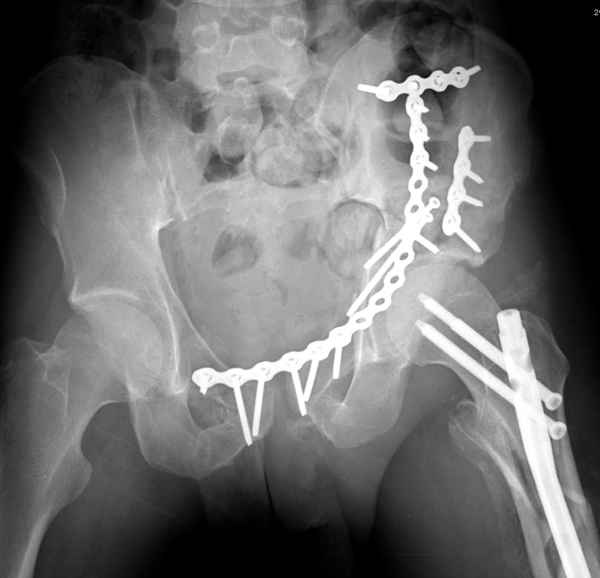

Из того минимума, что представлено, мне кажется, мы имеем дело с двухколонным переломом вертлужной впадины. Обычно медиальный (центральный) "вывих" головки встречаются в сложных двухколонных переломах со смещением.

По-моему, надо готовить больного к будущей артропластике, но без опоры на задний столб невозможно удержать протез. Опорная конструкция (кольца и т.д.) должны иметь опору, и поэтому мы бы сделали реостеосинтез задним доступом. При надобности остеотомия и рутинная фиксация с межколонными винтами.

Здесь несколько вариантов двухколонных свежих переломов, которые были оперированы из одного-заднего, а также из двух: переднего и заднего доступов.